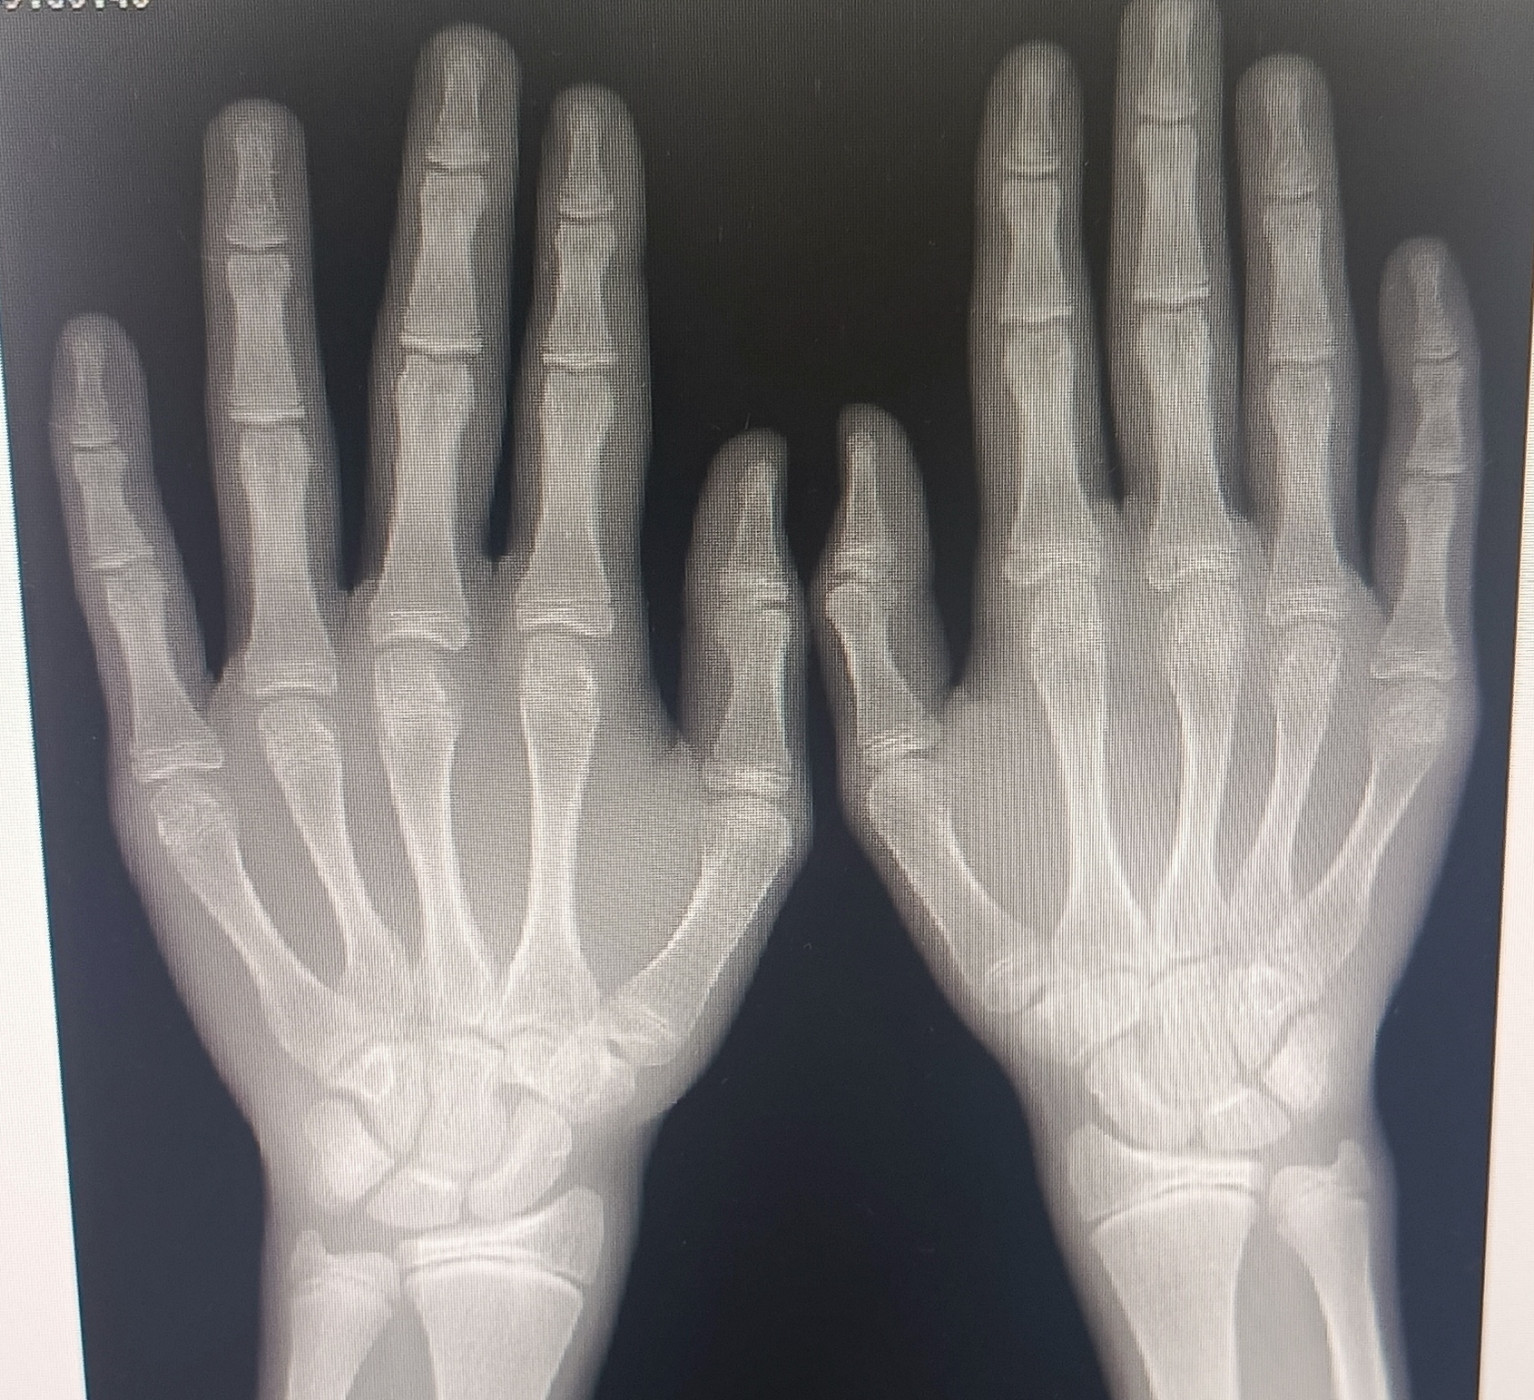

Костный возраст, зоны роста